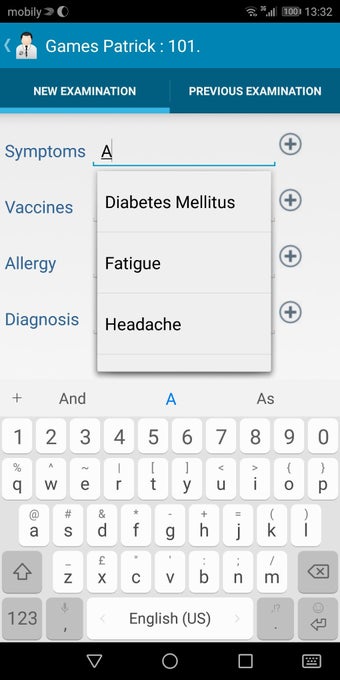

The Android Medical Records App by MedClin is a free medical records tracker app that allows users to store anamnesis, patient records, patient history, and health information. It is easy to use and provides numerous features such as username and password authentication, exporting medical data to Excel Sheet, and the ability to attach medical documents of any type. The app also has a smart search feature that allows users to search for patient information by name or ID, and even capture a photo for their profile.